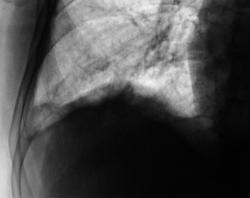

Сегодня произвели "очередной контроль". Произвели рентгенографию в прямой и правой боковой проекциях. Решили также произвести томографию в правой боковой проекции.

Катенёву В.Л.: На боковых томограммах, впечатление о инфильтрации с распадом в S10; томограммы, вероятно выполнены в положении лёжа, следовательо следует ожидать, что выпот растекся по грудной стенке и  не виден. С учётом характера распада, не исключаеиться туберкулёзный процесс.

О "выпоте" думали даже сначала, но только об осумкованном. Сегодня при дообследовании, "полостное образование" было неожиданной находкой, но о "туберкулёзной" этиологии, именно полостного образования, не думали. Но интересно, что пациент себя (с его слов) чувствует себя хорошо. ПО ВСЕЙ ВИДИМОСТИ, ОТПРАВИМ В ОБЛАСТЬ К ПУЛЬМОНОЛОГАМ.